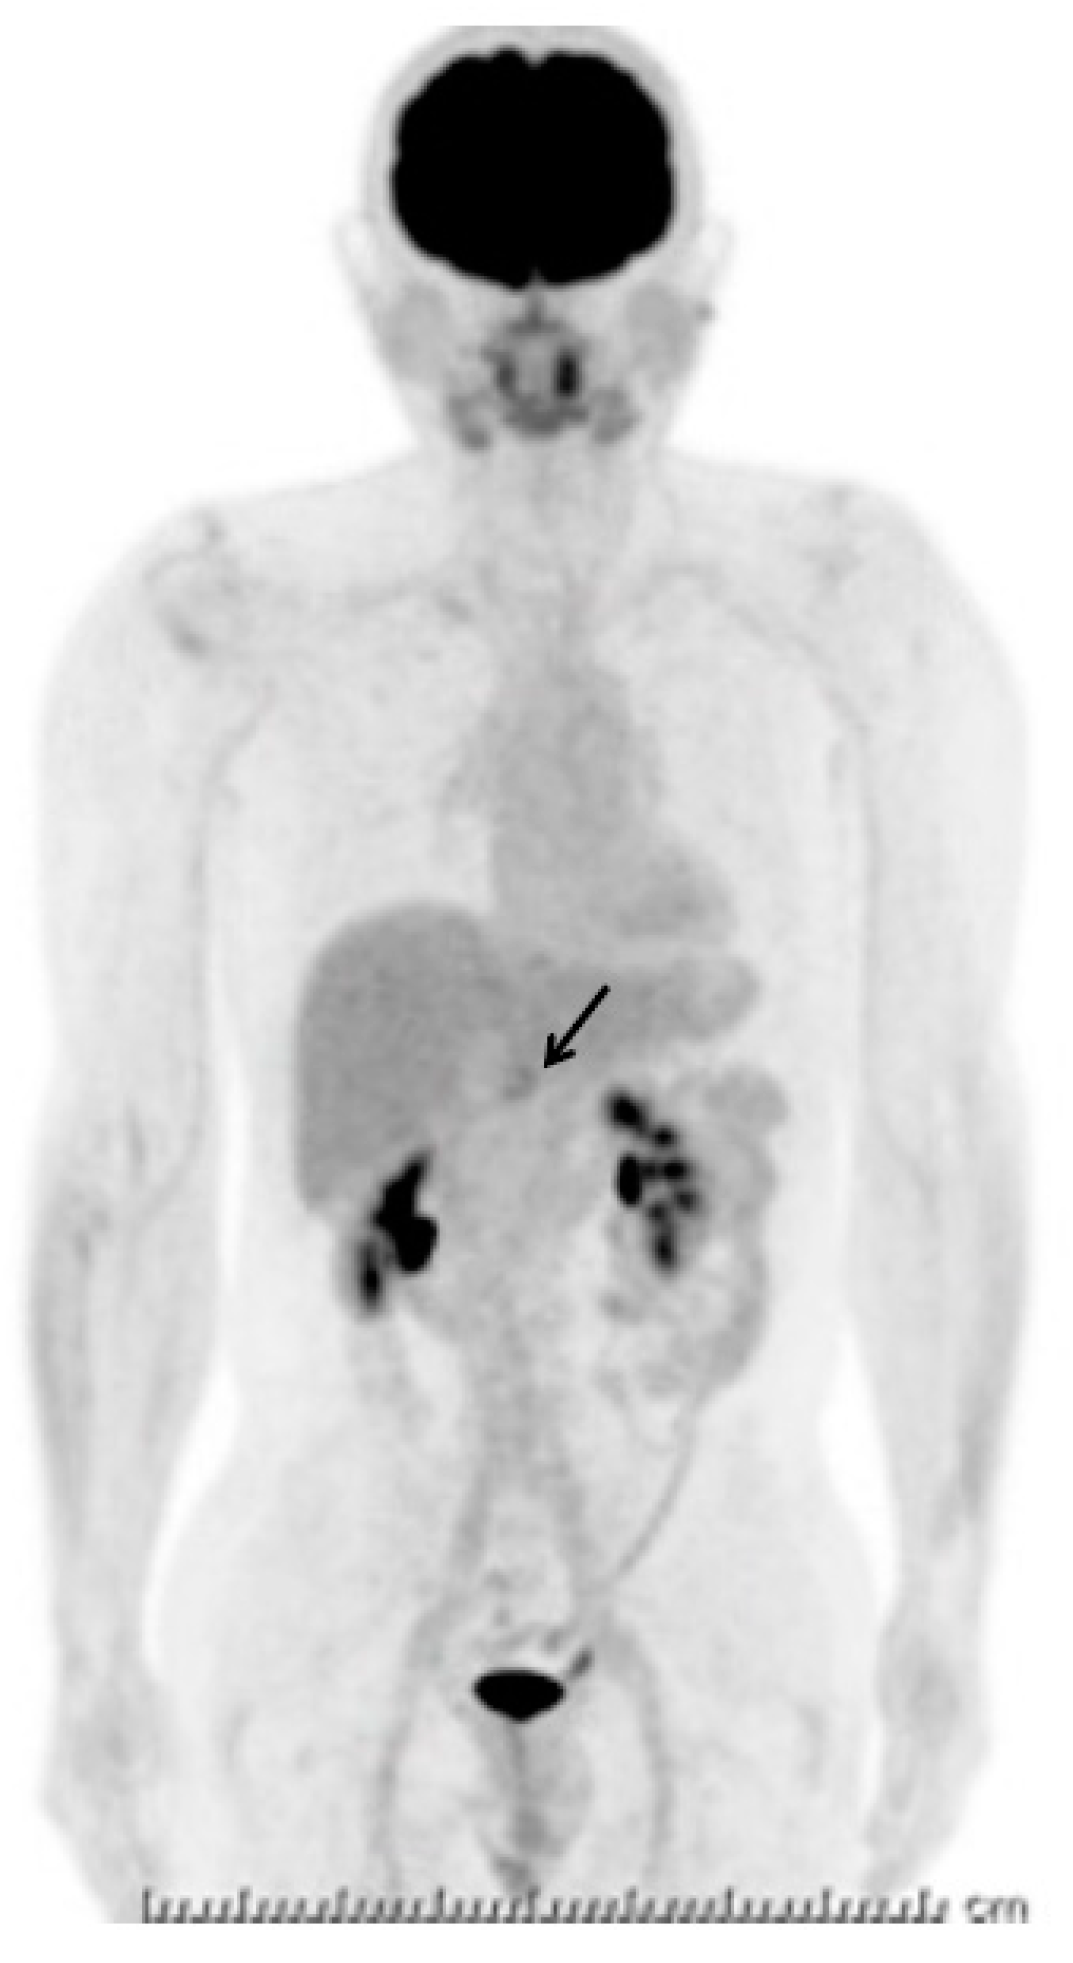

2. Case Presentation